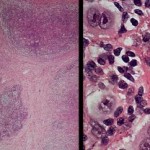

Alcuni ricercatori hanno identificato una strada per lo sviluppo di vaccini antinfluenzali universali. Ogni anno, l’influenza stagionale provoca gravi conseguenze in circa 3/5 milioni di persone ed è responsabile di circa 500.000  morti. La pandemia H1N1 del 2009, ha ucciso più di 14.000 persone in tutto il mondo. Nel frattempo, le preoccupazioni per la salute e per gli effetti del bioterrorismo da nuove mutazioni del gene H5N1 “influenza aviaria” virus, si sono intensificate. Le nuove mutazioni del gene H5N1, potrebbero facilitare l’infezione tra mammiferi ed esseri umani. Il team di ricercatori ha scoperto che l’H1N1 del 2009 , influenza aviaria vaccino, stimola gli anticorpi che proteggono contro molti virus influenzali tra cui il letale H5N1 ceppo influenza aviaria. La ricerca è stata pubblicata sulla rivista Frontierie in Immunologia. Il virus dell’influenza, spiegano i ricercatori, ha una proteina chiamata emoagglutinina o HA. Questa proteina è come un fiore, con una testa ed uno stelo. Il virus dell’influenza si lega alle cellule umane attraverso la testa di HA. Poichè HA muta molto rapidamente, è necessario sviluppare diversi vaccini ad ogni stagione. I vaccini contengono pezzi di geni molto deboli o morti che spingono il sistema immunitario a produrre anticorpi che circolano nel sangue per uccidere i geni specifici. Tuttavia il team di ricerca ha scoperto che il vaccino H1N1 del 2009, ha indotto anticorpi protettivi ampiamente in grado di combattere diverse varianti del virus dell’influenza.  La nuova scoperta potrebbe aprire la strada allo sviluppo di vaccini antinfluenzali universali. Il team di scienziati è composto da ricercatori dell’Università di Ottawa e Toronto, dall’Agenzia per la tutela e la promozione della  salute dell’Ontario e dal Centro BC for Disease Control.